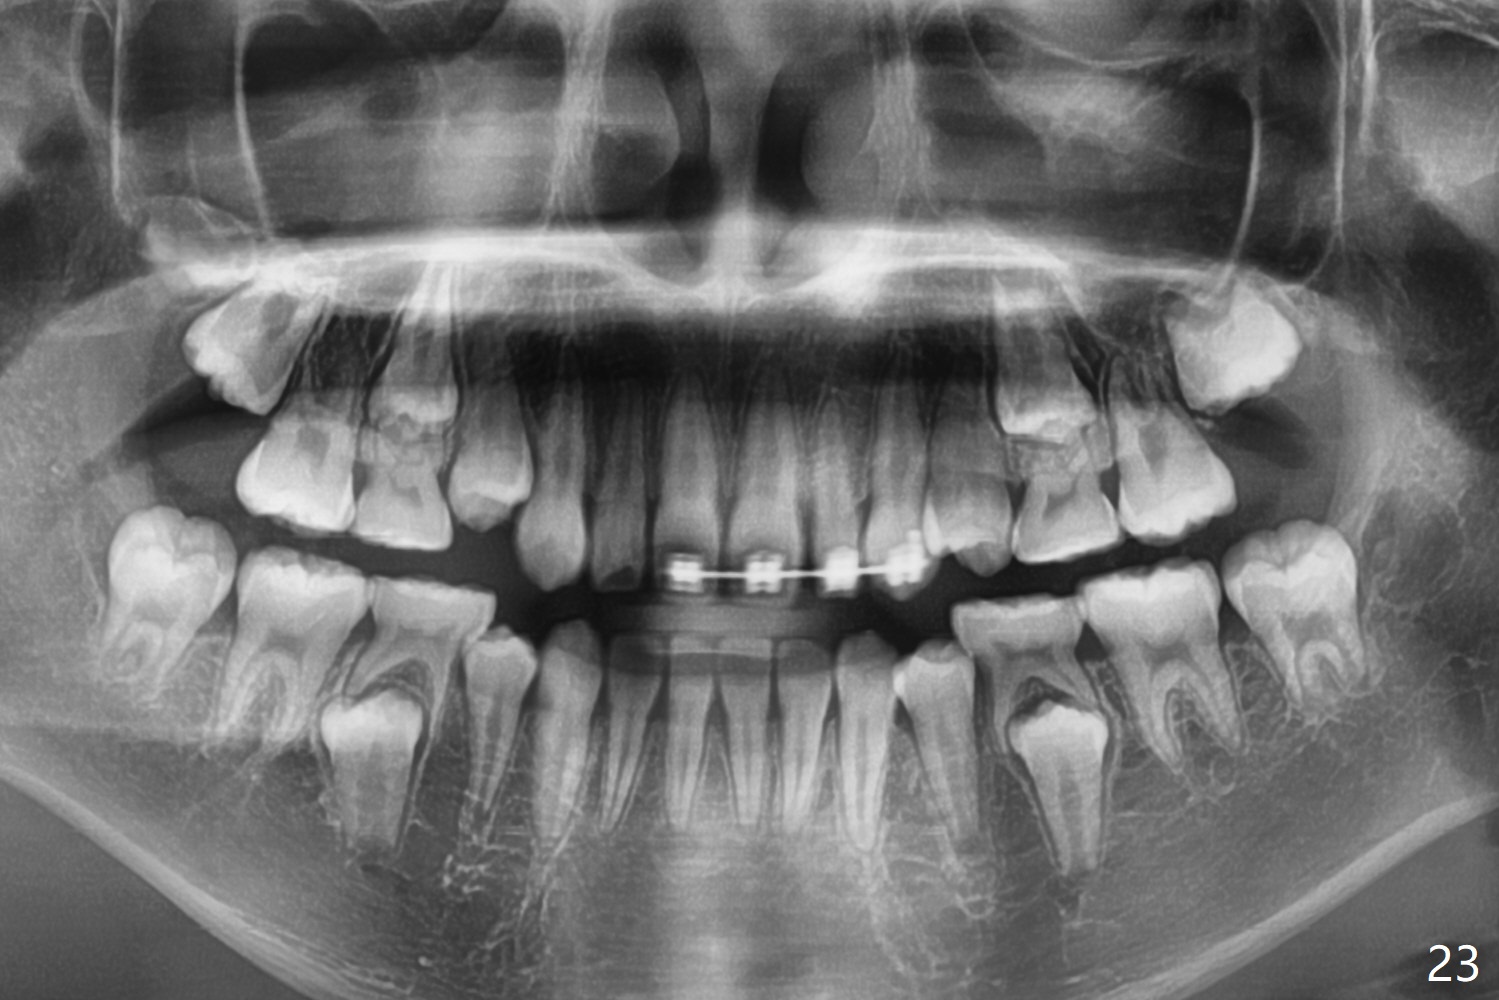

OK Xin, just evaluated the case. If she started with the anterior dental crossbite and you are barely over-corrected right now, I would be very comfortable discontinuing treatment. At her age, there is nothing that can no longer be dealt with beautifully when it is more age appropriate.When anterior cross bite is corrected 19 months post banding, the tooth #10 (microdontia) has tendency of edge-to-edge (Fig.16,17). Power chains are used to create space for #11 to erupt fully before bracketing. In spite of the effort, the peg lateral remains edge-to-edge 23 months post banding (Fig.18,19). The segmental 19x26 braided wire retains as a retainer to prevent #10 from cross bite. The facial profile is more or less normal immediately post debracketing (Fig.20). The anterior occlusion appears to remain basically the same 7 months post debracketing (Fig.21,22). UR3 erupts, while the diastema mesial to UL2 enlarges so that the arch wire appears shorter. UL2,3 appear to be in cross bite 14 months post debracketing, while Es retain at the age of 13 (delayed development, Fig.23).